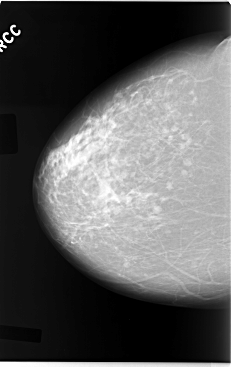

C_0044_1.RIGHT_CC